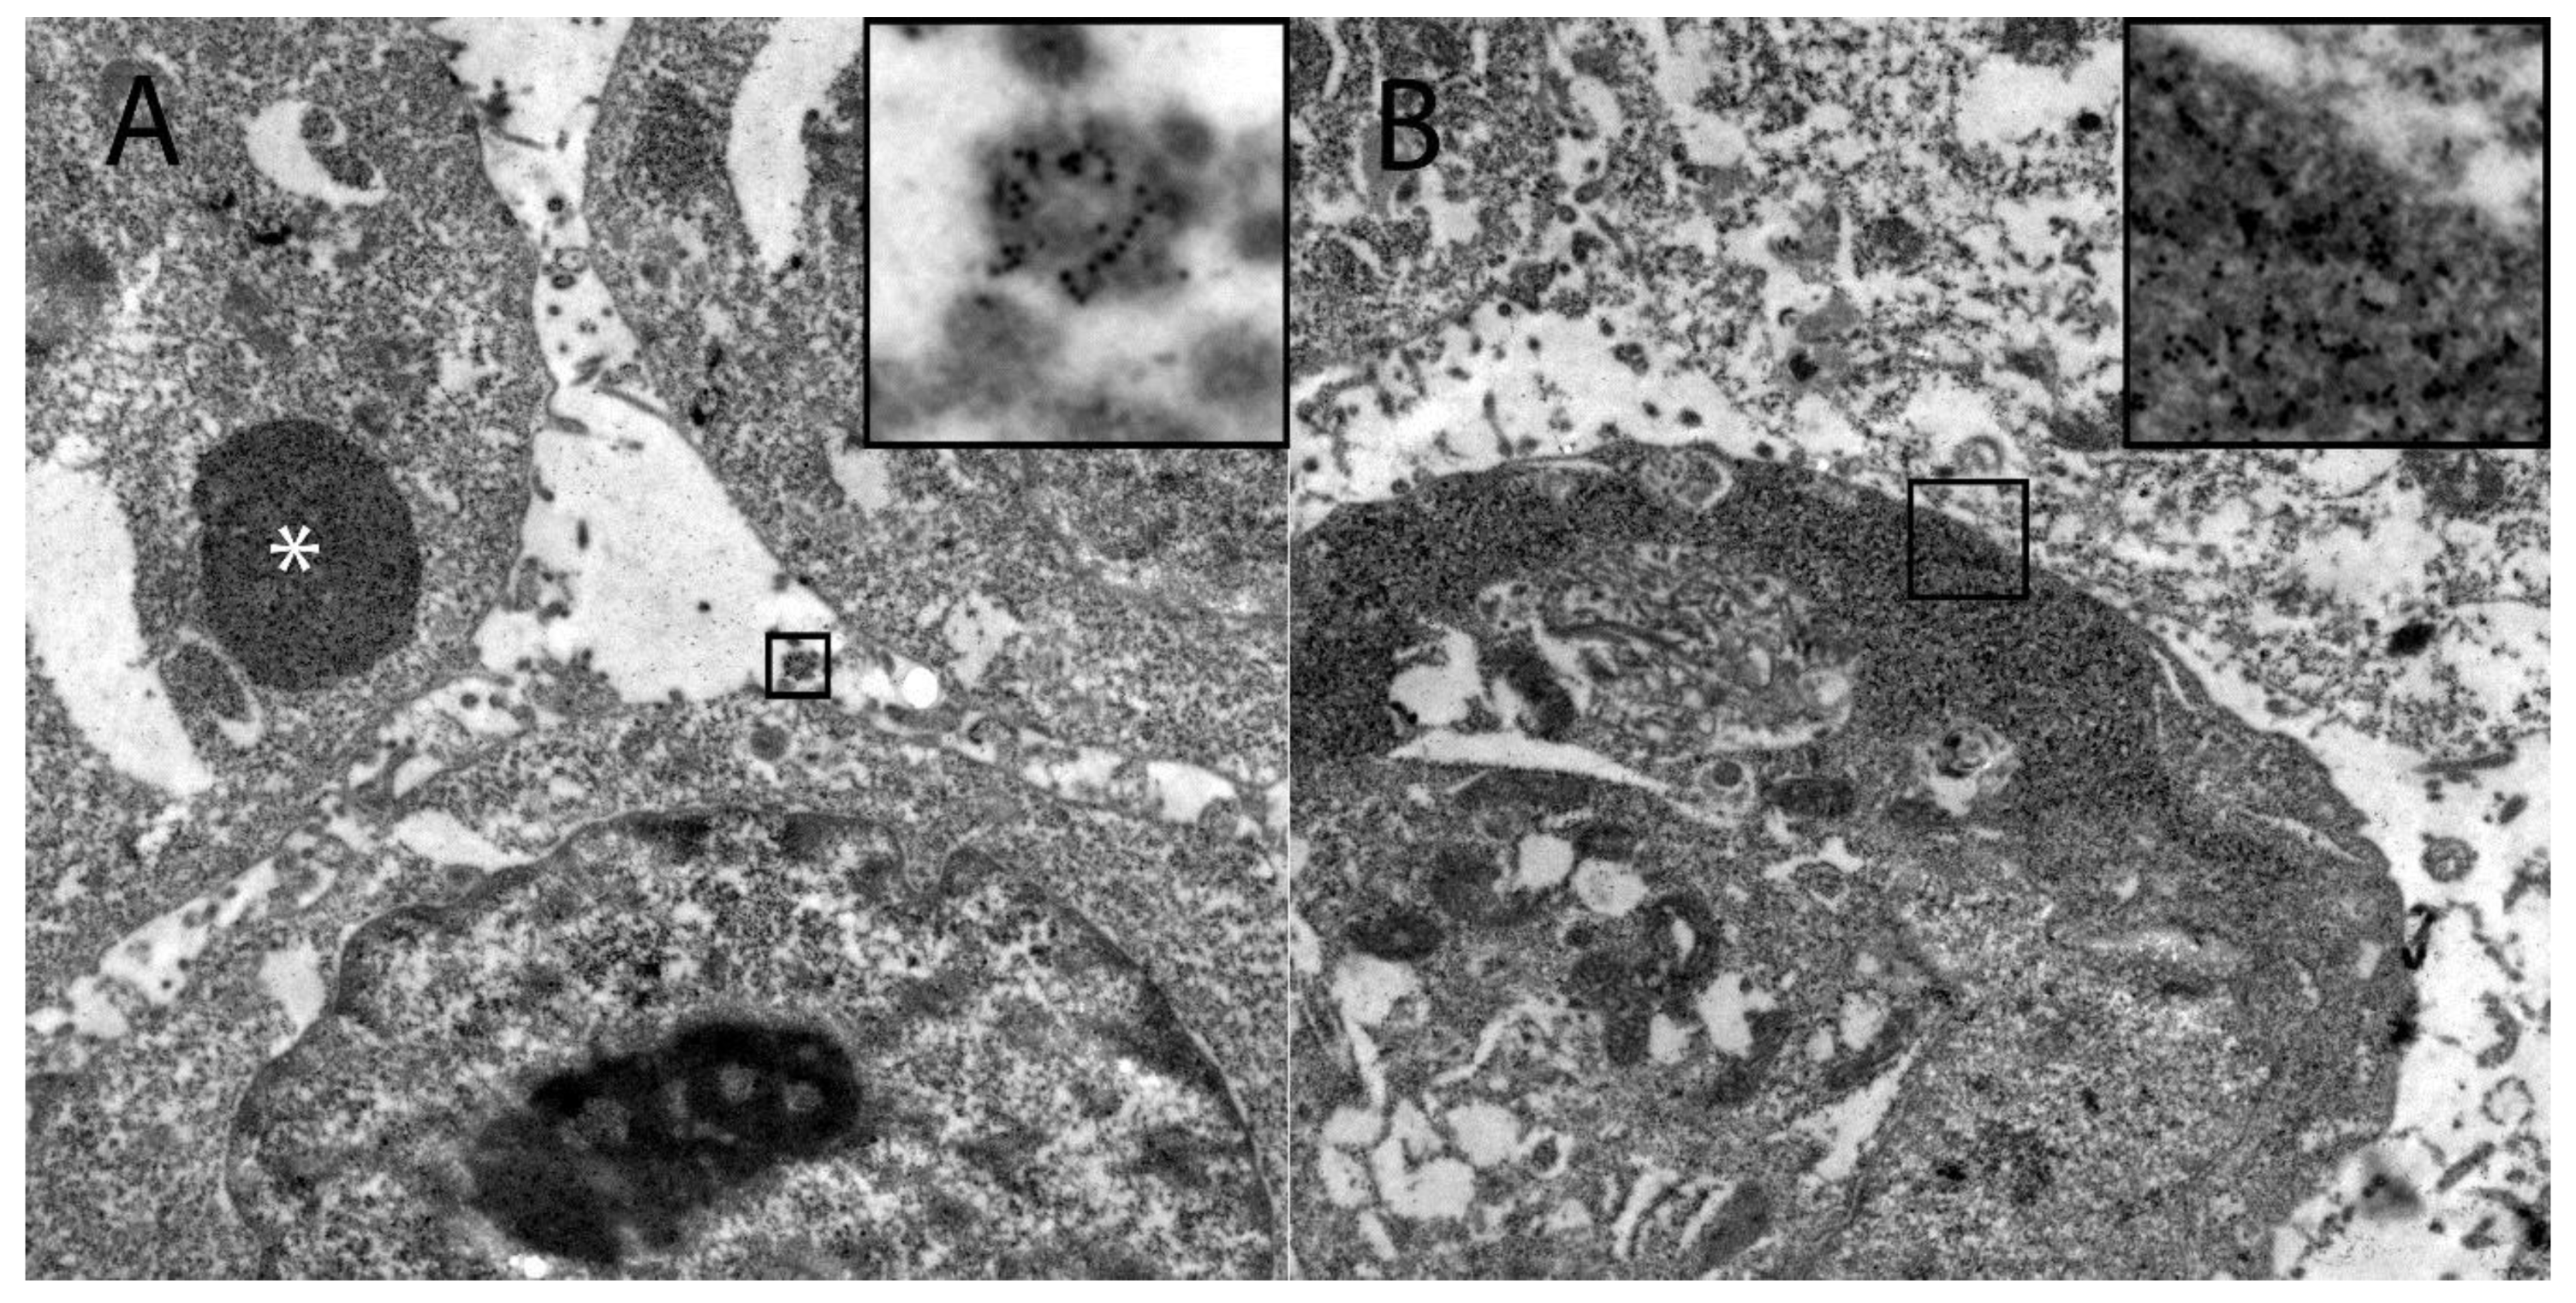

Ultrastructural investigation of DH82Ond pi by immunoelectron microscopy for HIF-1α revealed that this protein was mostly localized in the sub-membranous compartment as well as within variably sized, round, moderately to highly electrondense vesicles (Figure 5).

Figure 5.

Demonstration of the intracellular HIF-1α localization in persistently canine distemper virus infected DH82 cells as determined by immunoelectron microscopy. (A) HIF-1α was found within variably sized, round, moderately to highly electrondense vesicles (insert) and in large moderately electrondense vacuoles (*). Additionally, HIF-1α was detected often in the sub-membranous area of the cytoplasm (insert; B). Magnification 9000×.